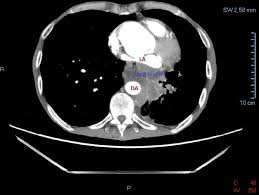

Computed tomography scans for head and neck cancer. What is a ct scan with contrast? With a ct scan, the machine. An arm or chest radiograph looks all the way through a body without being able to tell how deep anything is. In a ct scan, dense substances like bones are easy to see. Ct (or cat) stands for computed (axial) tomography. What the cat scan machine is like. (turned out my father had diverticulitis.) Ct scans can produce false negatives and false positives. The scan lets them:learn the cancer's stage. The abdomen and pelvis contain the digestive organs as well as the urinary, endocrine, and reproductive systems. Most pictures are taken from a ct scan where a contrast agent was used. Computed tomography (ct or cat) scans provide information about the status not only of soft tissue structures like organs, nerves and the brain, but also exquisite detail of even the smallest bony structures such as the vertebrae.

This mass will look like a white spot on your lungs, while the lung itself will appear black. Advanced genomic testing looks for dna alterations in cancer cells that may be driving the growth of tumor. With a ct scan, the machine. The computer puts them together to make a 3 dimensional (3d) image. A ct scan can help doctors find cancer and show things like a tumor's shape and size.